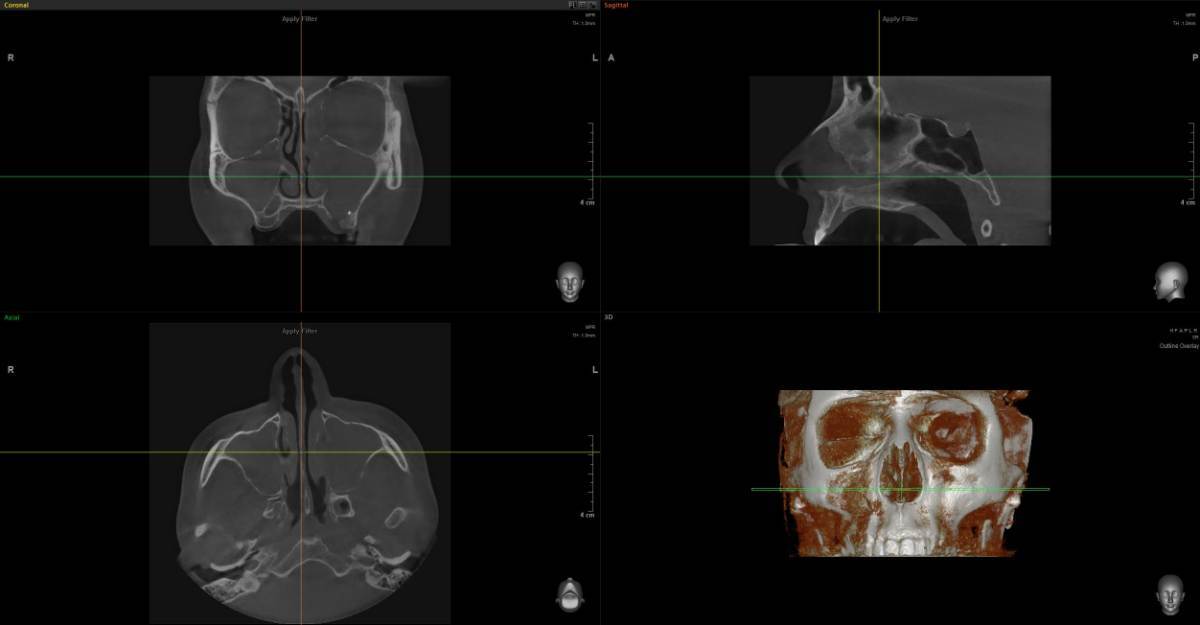

Анна1402 Опубликовано 6 марта Поделиться Опубликовано 6 марта Здравствуйте. Нужно второе мнение. Отправляю два КТ с разницей в три месяца. Первое после удаления. [🗣 «Ситуация такая: 28 ноября отошла коронка, чтобы ее снять, пришлось несколько раз ударять по зубу, решили не распиливать, чтобы сэкономить деньги. По зубу я получила около 30 или более ударов, коронку приклеили обратно, через три дня завоняло тухло. зуб пришлось удалить, была перфорация, перфорацию заложили губками и зашили, через три дня завоняло снова, в процессе этого всего два раза пропивала антибиотики. В конце Декабря хотела сдаться лорам, но так как это было перед праздниками, они меня не взяли, и сказали, что вообще операцию должен вам делать челюстно лицевой хирург, так как у меня дома младенец, я с радостью ушла и решила, буду пока справляться сама, промывала гипертоническим раствором соли, и мне стало лучше, то есть гноя у меня стало меньше, лунка у меня заросла хорошо, показывала челюстно лицевым хирургам, перфорации нет, немного стекает по задней стенке гной, но с каждым днем все меньше и пульсирует левая пазуха, правая, не скажу, что пульсирует, не болит, но были немного выделения, вопрос: на первом Кт, забита одна пазуха, и чем она забита, на втором Кт уже забиты две, хотя чувствую я себя лучше, нос у меня дышит, на первом Кт, когда я делала нос, у меня не дышал, сейчас нос у меня дышит, правая ноздря дышит, ну, вполне нормально, по сравнению с левой. Вот вопрос: делать ли операцию, можно ли ждать, и чем заполнены пазухи: гноем, отек это, или какие то инородные тела? Что это и что вы посоветуете Спойлер Вопрос: почему мне как будто лучше, а на снимке хуже. Что в пазухах? И почему правая стала тоже забита. И сдаться ли 17 марта в больницу к чхл на микрогаморотомию через губу? Заранее очень благодарю за время, которое уделите. Спасибо доктора! https://disk.yandex.ru/d/sTb5_xcHWQVHIw https://disk.yandex.ru/d/1ccGILTzDB1k0g Ссылка на комментарий

Женька Опубликовано 8 марта Поделиться Опубликовано 8 марта @Анна1402 здравствуйте, чем заполнены пазухи по снимкам сказать невозможно. Можно лишь точно сказать, что пазухи тотально затенены (в пазухах что-то есть, гной, кровь, кисты или опухоль). Соустье судя по всему не функционирует. Я бы наоборот через лоров делал. Так как не вижу никаких показаний, идти к ЧЛХ на гайморотомию. Чем делать дырки - лучше эндоскопически зайти в пазуху и санировать. Но перед этим - приём грамотного ЛОР-врача. 1 1 Ссылка на комментарий